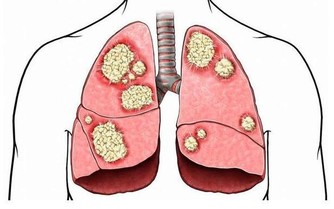

日前一名16歲腦性麻痺少女因發燒3天、食欲不振、便秘且嚴重貧血而就醫,經過進一步檢查,才發現少女已經大腸癌末期無法再做積極治療,僅能做症狀治療舒緩其不適。近幾年來大腸癌有年齡層下降的趨勢,專家建議家長特別留意孩子症狀,才能有助及早發現、提早治療。

據《自由時報》報導,這名罹病少女無家族病史,體重較同齡者輕且飲食上並無特別偏重,攝取高油脂及刺激性的食物,但由於少女本身有表達上困難,導致症狀更不易發現,一旦發現,為時已晚。

專家提醒人們要重視腸癌發病率呈年輕化趨勢。兒童如出現腹部不適、不明原因的腹痛、大便習慣改變、便中帶血和黏液時要想到結腸癌的可能,儘早到正規醫院就診,爭取早期診斷、早期治療。

大腸癌多見於40歲以上的中年人,發生在兒童則十分少見。由於結腸癌起病較隱匿,早期癥狀不明顯,且無特異性,加之人們不易想到兒童能患結腸癌,往往易誤診為其他疾病。所以兒童結腸癌易延誤診斷,就診時常屬晚期,且常並發腸梗阻,預後較差。

目前大腸癌的治療,以手術切除為最主要的方法,只要早期發現,早期手術切除乾淨,預後很好。化學治療與放射線治療是輔助治療,通常用來減少復發或減輕症狀